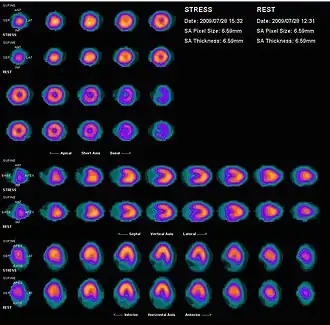

Nuclear medicine myocardial perfusion scan with thallium-201 for the rest images (bottom rows) and Tc-Sestamibi for the stress images (top rows). The nuclear medicine myocardial perfusion scan plays a pivotal role in the non-invasive evaluation of coronary artery disease. The study not only identifies patients with coronary artery disease; it also provides overall prognostic information or overall risk of adverse cardiac events for the patient.

Nuclear medicine myocardial perfusion scan with thallium-201 for the rest images (bottom rows) and Tc-Sestamibi for the stress images (top rows). The nuclear medicine myocardial perfusion scan plays a pivotal role in the non-invasive evaluation of coronary artery disease. The study not only identifies patients with coronary artery disease; it also provides overall prognostic information or overall risk of adverse cardiac events for the patient. -